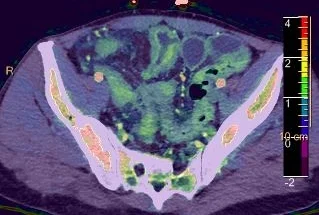

40 yo M, no prior history, subacute abdominal pain.

CT with iodine density overlay nicely depicts mucosal hypervascularity in the ileum. Also note the small ulcer in ileum.